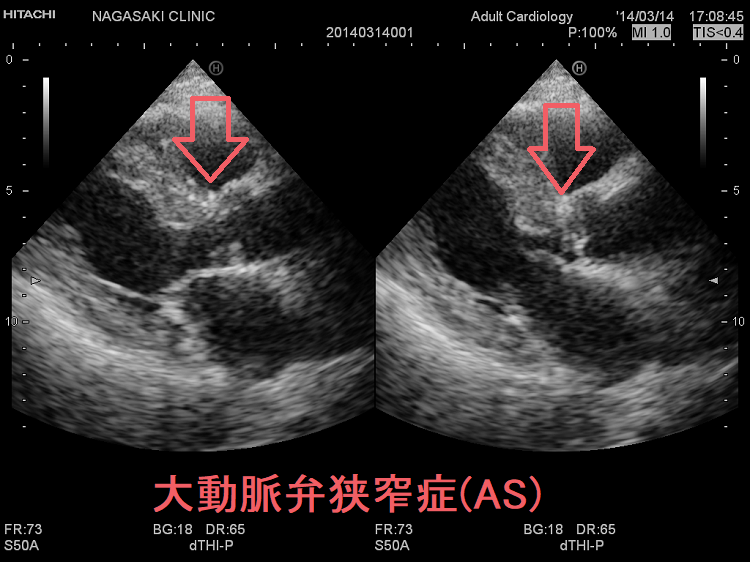

大動脈の動脈硬化が大動脈弁に達し、弁が(ガチガチに)石灰化すると開きが悪くなります[加齢性大動脈弁狭窄症(AS)]。

大動脈弁狭窄症(AS)では、

- 心拍出量が低下、冠動脈血流が減少して狭心症を発症

- 脳血流が減少し失神が現れると3年の命(余命3年)とされる

- 胸骨右縁第2肋間を最強点とする収縮期雑音が頚部へ放散

- 心電図 I, aVL, V5-6 誘導でST低下と深い陰性T波をともなう左室肥大(ストレインパターン)が特徴的

大動脈弁狭窄症(AS)の心筋では、おそらく3型脱ヨード酵素(DIO 3)発現により、甲状腺ホルモンの不活性化が促進されています[Thyroid. 2017 May;27(5):738-745.]。おそらく、心筋を保護するための生理的代償反応